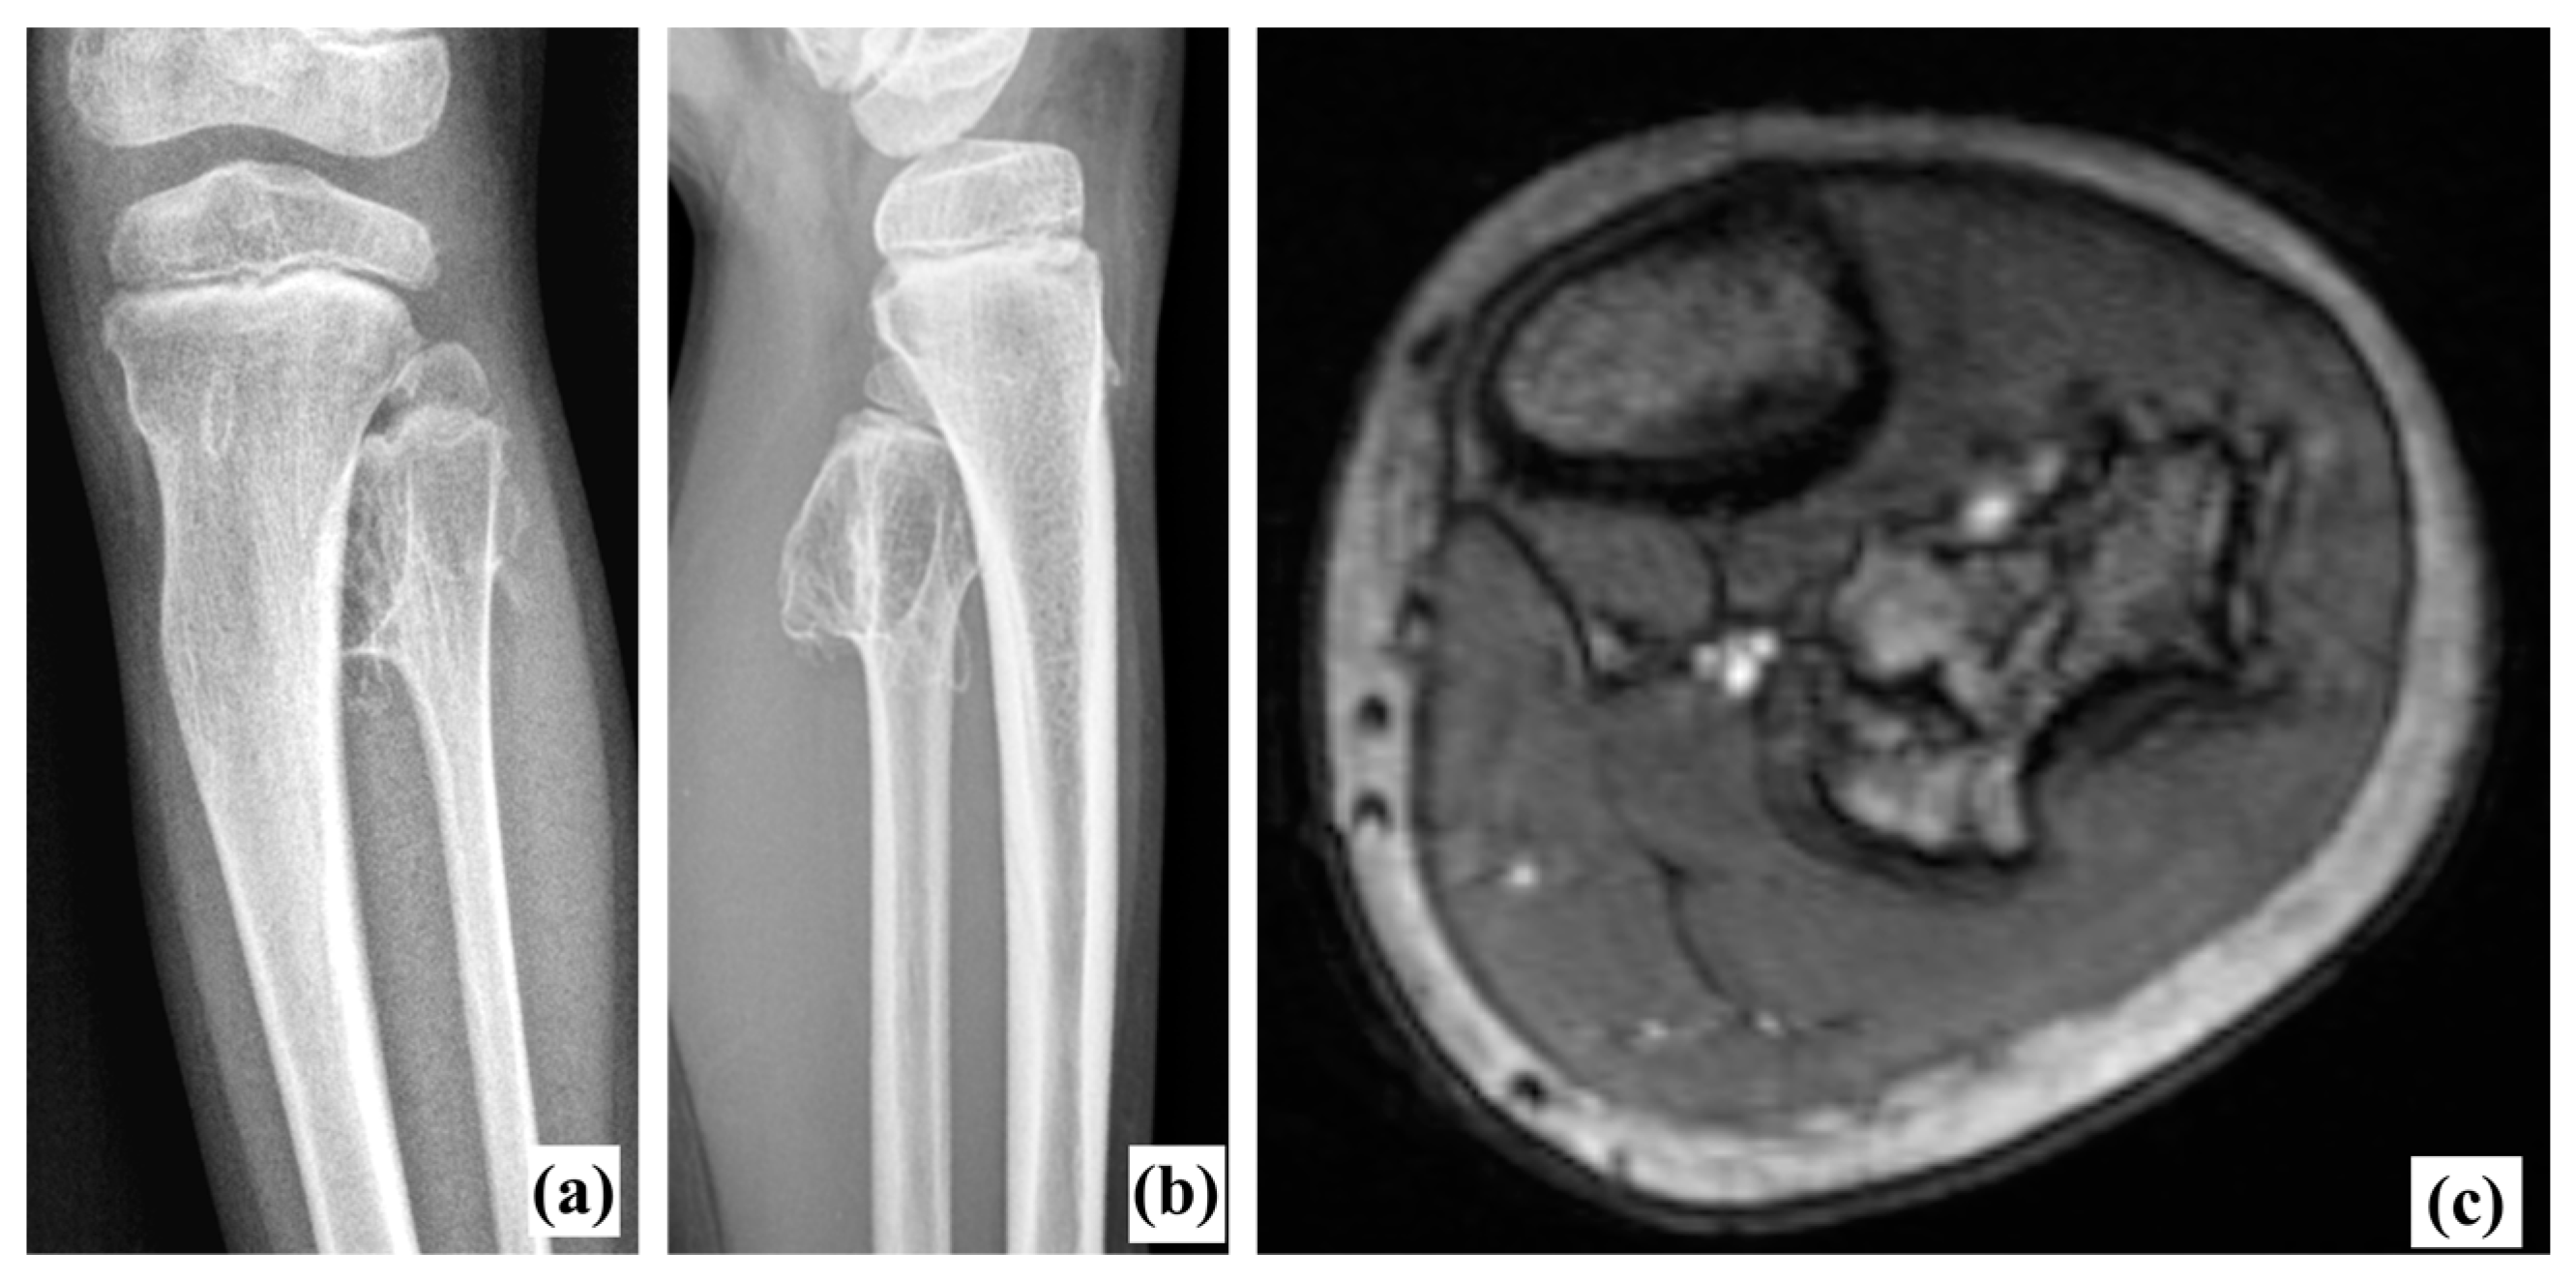

Radiography (Figure 1a,b) revealed a voluminous inter-tibio-fibular osteochondroma developed from fibular proximal metaphysis. The approximate dimensions of the bone tumor were about 4/3/2 cm (cranio-caudal/antero-posterior/latero-lateral). The lesion had all the characteristics of an exostosis [3]: benign-appearing bone lesion, bony excrescence with well-defined margins, thin outer cortex which flares from the host bone cortex and internal lesion in cancellous bone which blends with the cancellous bone of the metaphysis [3]. There was no sign of adjacent bone scalloping, but bowing of the tibia was present. We also performed an MRI exam which confirmed the lesion and showed close relation to the tibiofibular trunk and the anterior tibial artery, but without any sign of compression (Figure 1c). Long-leg radiographs showed valgus deformity of the tibia (HKA angle: 166°, MAD: 29 mm) (Figure 2).

Figure 1. Preoperative X-rays (a,b) and MRI (c). Anterior tibial artery and tibiofibular trunk were immediately close to the exostosis.